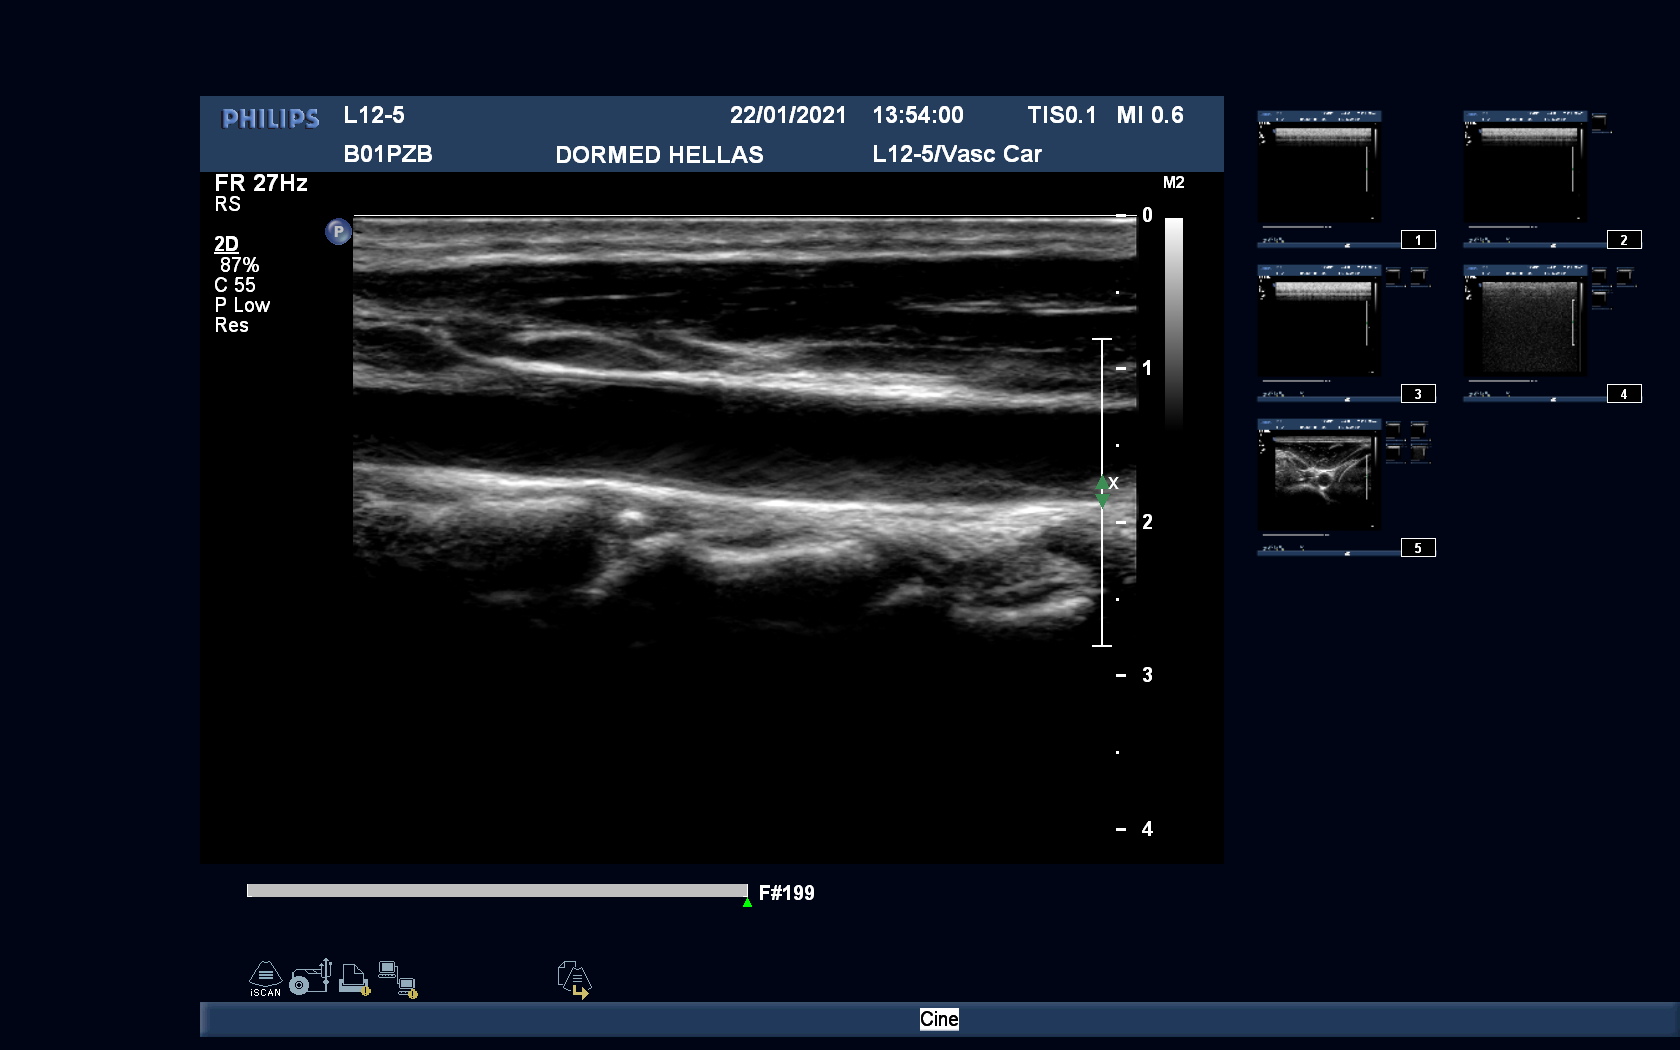

Philips L12-5 Vascular Linear Refurbished

Philips Linear L12-5 Vascular

Intended use

Vascular, Small Parts, Breast and Superficial

Frequency Range

12 – 5 MHz

System compatibility

iE33, iU22, HD15

Philips L12-5 Vascular Linear

Frequency Range: 12 – 5 MHz

Philips L12-5 Vascular Linear for Vascular, Small Parts, Breast and Superficial